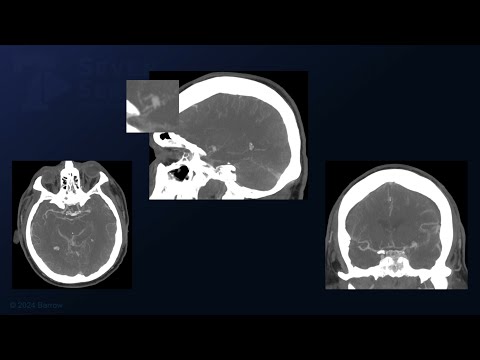

Hellow guys, Welcome to my website, and you are watching Ruptured R MCA Aneurysm. Samer Hoz. 5.1.2021 Iraq. and this vIdeo is uploaded by HOZ NeuroSurgery at 2021-01-05T11:07:12-08:00. We are pramote this video only for entertainment and educational perpose only. So, I hop you like our website.